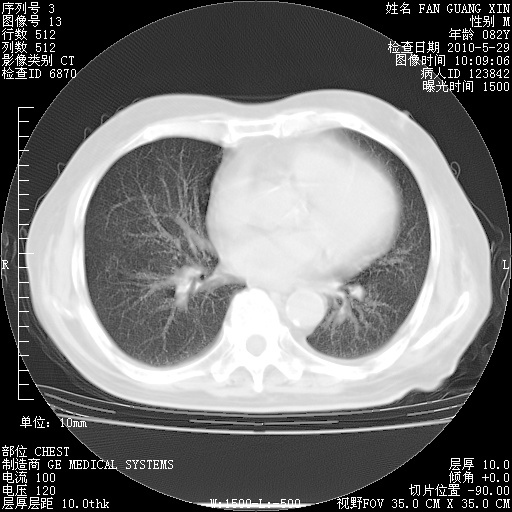

发表于 2010-5-19 19:23

还需要哪些辅助检查?我们医院排除真菌感染没有任何检验方法,胸片好像能够排除肺部真菌感染。

补充:ENA化验全部阴性。免疫五项(IgG、IgA、IgM、C3、C4)只有C4略高。

CD3+ T细胞/淋巴细胞 46% (参考值50.00~84.00%)

CD3+CD4+ T细胞/淋巴细胞 21% (参考值27.00~51.00%)

CD3+CD8+ T细胞/淋巴细胞 25% (参考值15.00~44.00%)

CD3+CD4+ T细胞/CD3+CD8+ T细胞 0.84 (参考值0.71~2.78)

T细胞亚群是治疗5天采血。